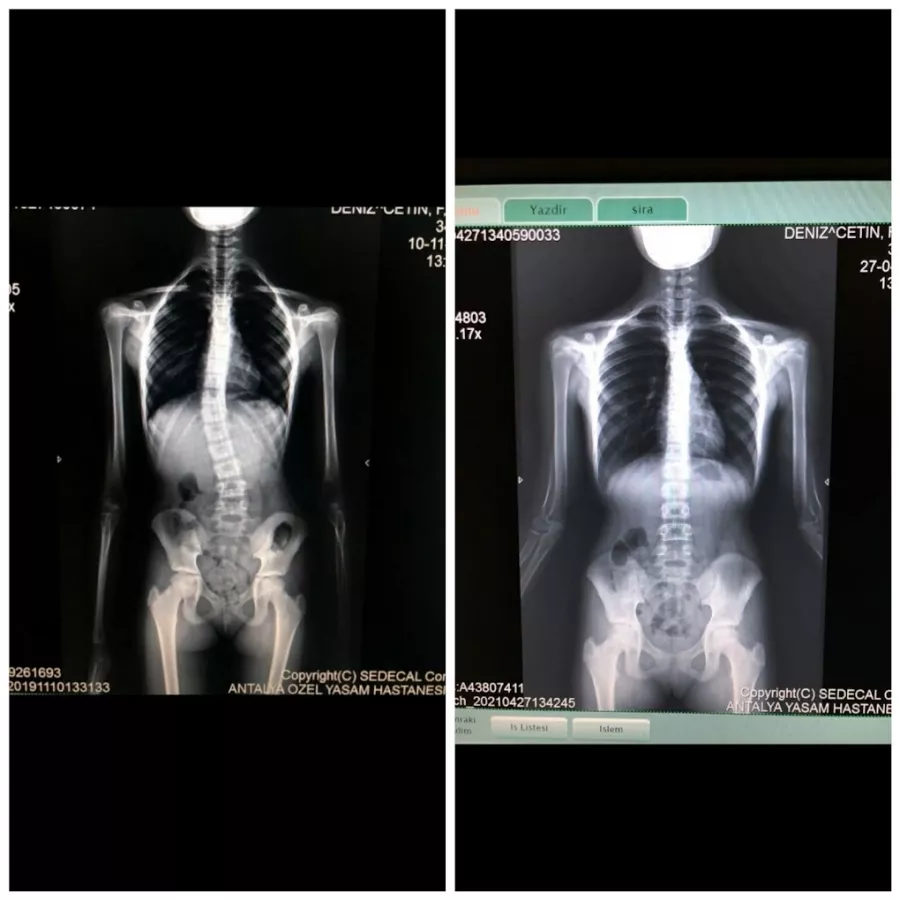

Эти потребности могут включать в себя различные формы, такие как поддержание формы, улучшение физической формы или облегчение ноя в мышцах и суставах, а также выполнение поддерживающих программ упражнений для устранения проблем, вызванных нарушением осанки, походки, нарушениями системы кровообращения или анатомическими нарушениями в структуре позвоночника.

По этой причине в процессе, который начинается с оценок наших физиотерапевтов, мы тщательно применяем созданные индивидуальные программы и продолжаем регулярно следить за нашими членами, которые завершили свои программы в случае необходимости.